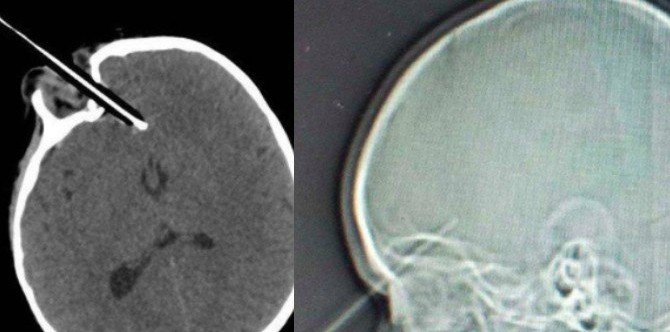

Gambar x-ray di atas menunjukkan mata tercucuk pensil dengan pensil yang telah tertembus masuk 1 1/2 inci ke bahagian depan otaknya.

Nasib baik kanak-kanak dengan mata tercucuk pensil ini berjaya diselamatkan!

Wren terpaksa menjalani pembedahan yang mengambil masa 4 jam. Selepas menjalani pembedahan, doktor melaporkan pembedahan berjaya dan Wren dalam keadaan yang stabil.

Nasib baik, pensil yang tembus masuk itu berjaya mengelak bebola mata serta saluran-saluran darah utama! Doktor yang melakukan pembedahan menarik nafas lega apabila mendapati pensil itu hanya menembusi ruang antara bebola mata dan soket mata kanak-kanak itu saja.